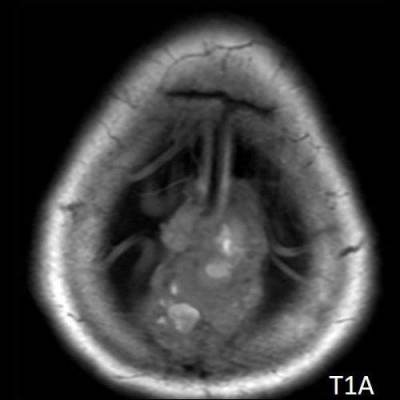

- A) Vertekste, orta hatta, multikistik, T2A sekanslarda yoğun içerikli sıvı-sıvı seviyelenmesi (oklar) ve T1A sekanslarda hiperintens, SWI sekanslarda blooming artefaktı oluşturan, belirgin düşük ADC değerlerine sahip, kanama alanları içeren (oklar) kitlesel lezyon mevcuttur.

- MR görüntülemede genellikle T1 ağırlıklı görüntülerde gri cevher ile izointens, T2 ağırlıklı görüntülerde hiperintens, heterojen kontrast tutulumu gösteren kitlesel lezyon izlenir. Nekrotik, hemorajik, kistik alanlar içerebilir. Kanamaya bağlı sıvı-svı seviyeleri izlenebilir.